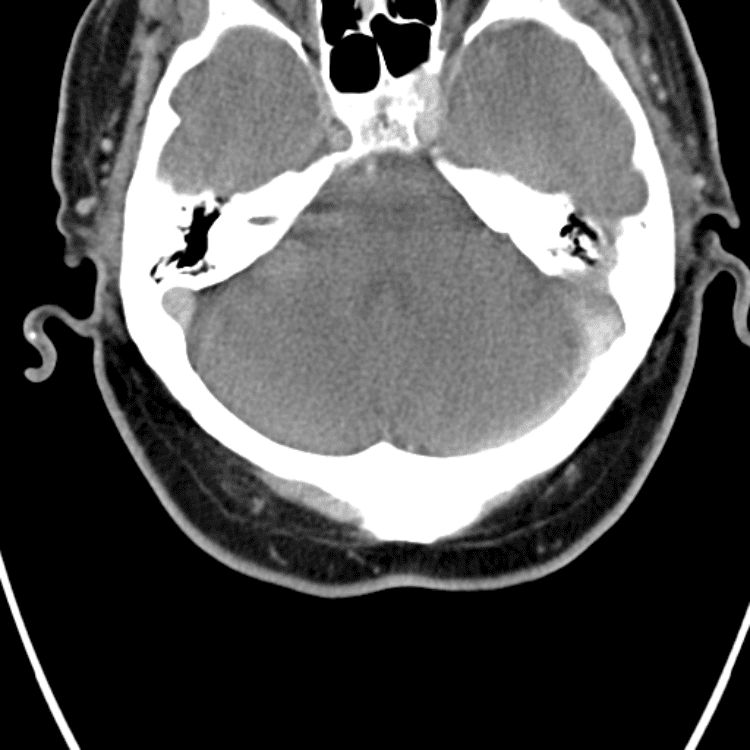

Head and Neck

Simulates call by including subtle or difficult cases and some normals.